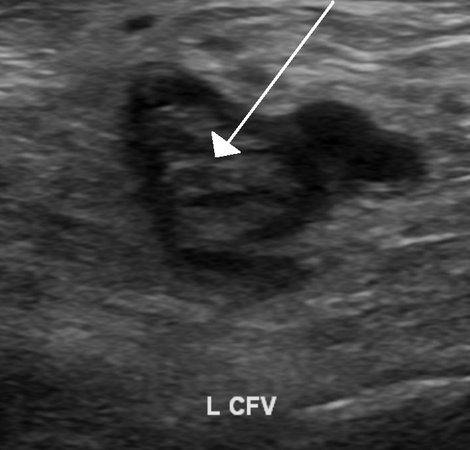

Υπερηχογραφία (Ultrasound): Ο υπέρηχος μπορεί να χρησιμοποιηθεί για την αξιολόγηση των φλεβών στα πόδια, όπου συχνά προκύπτουν οι θρόμβοι που μπορούν να προκαλέσουν πνευμονική εμβολή.